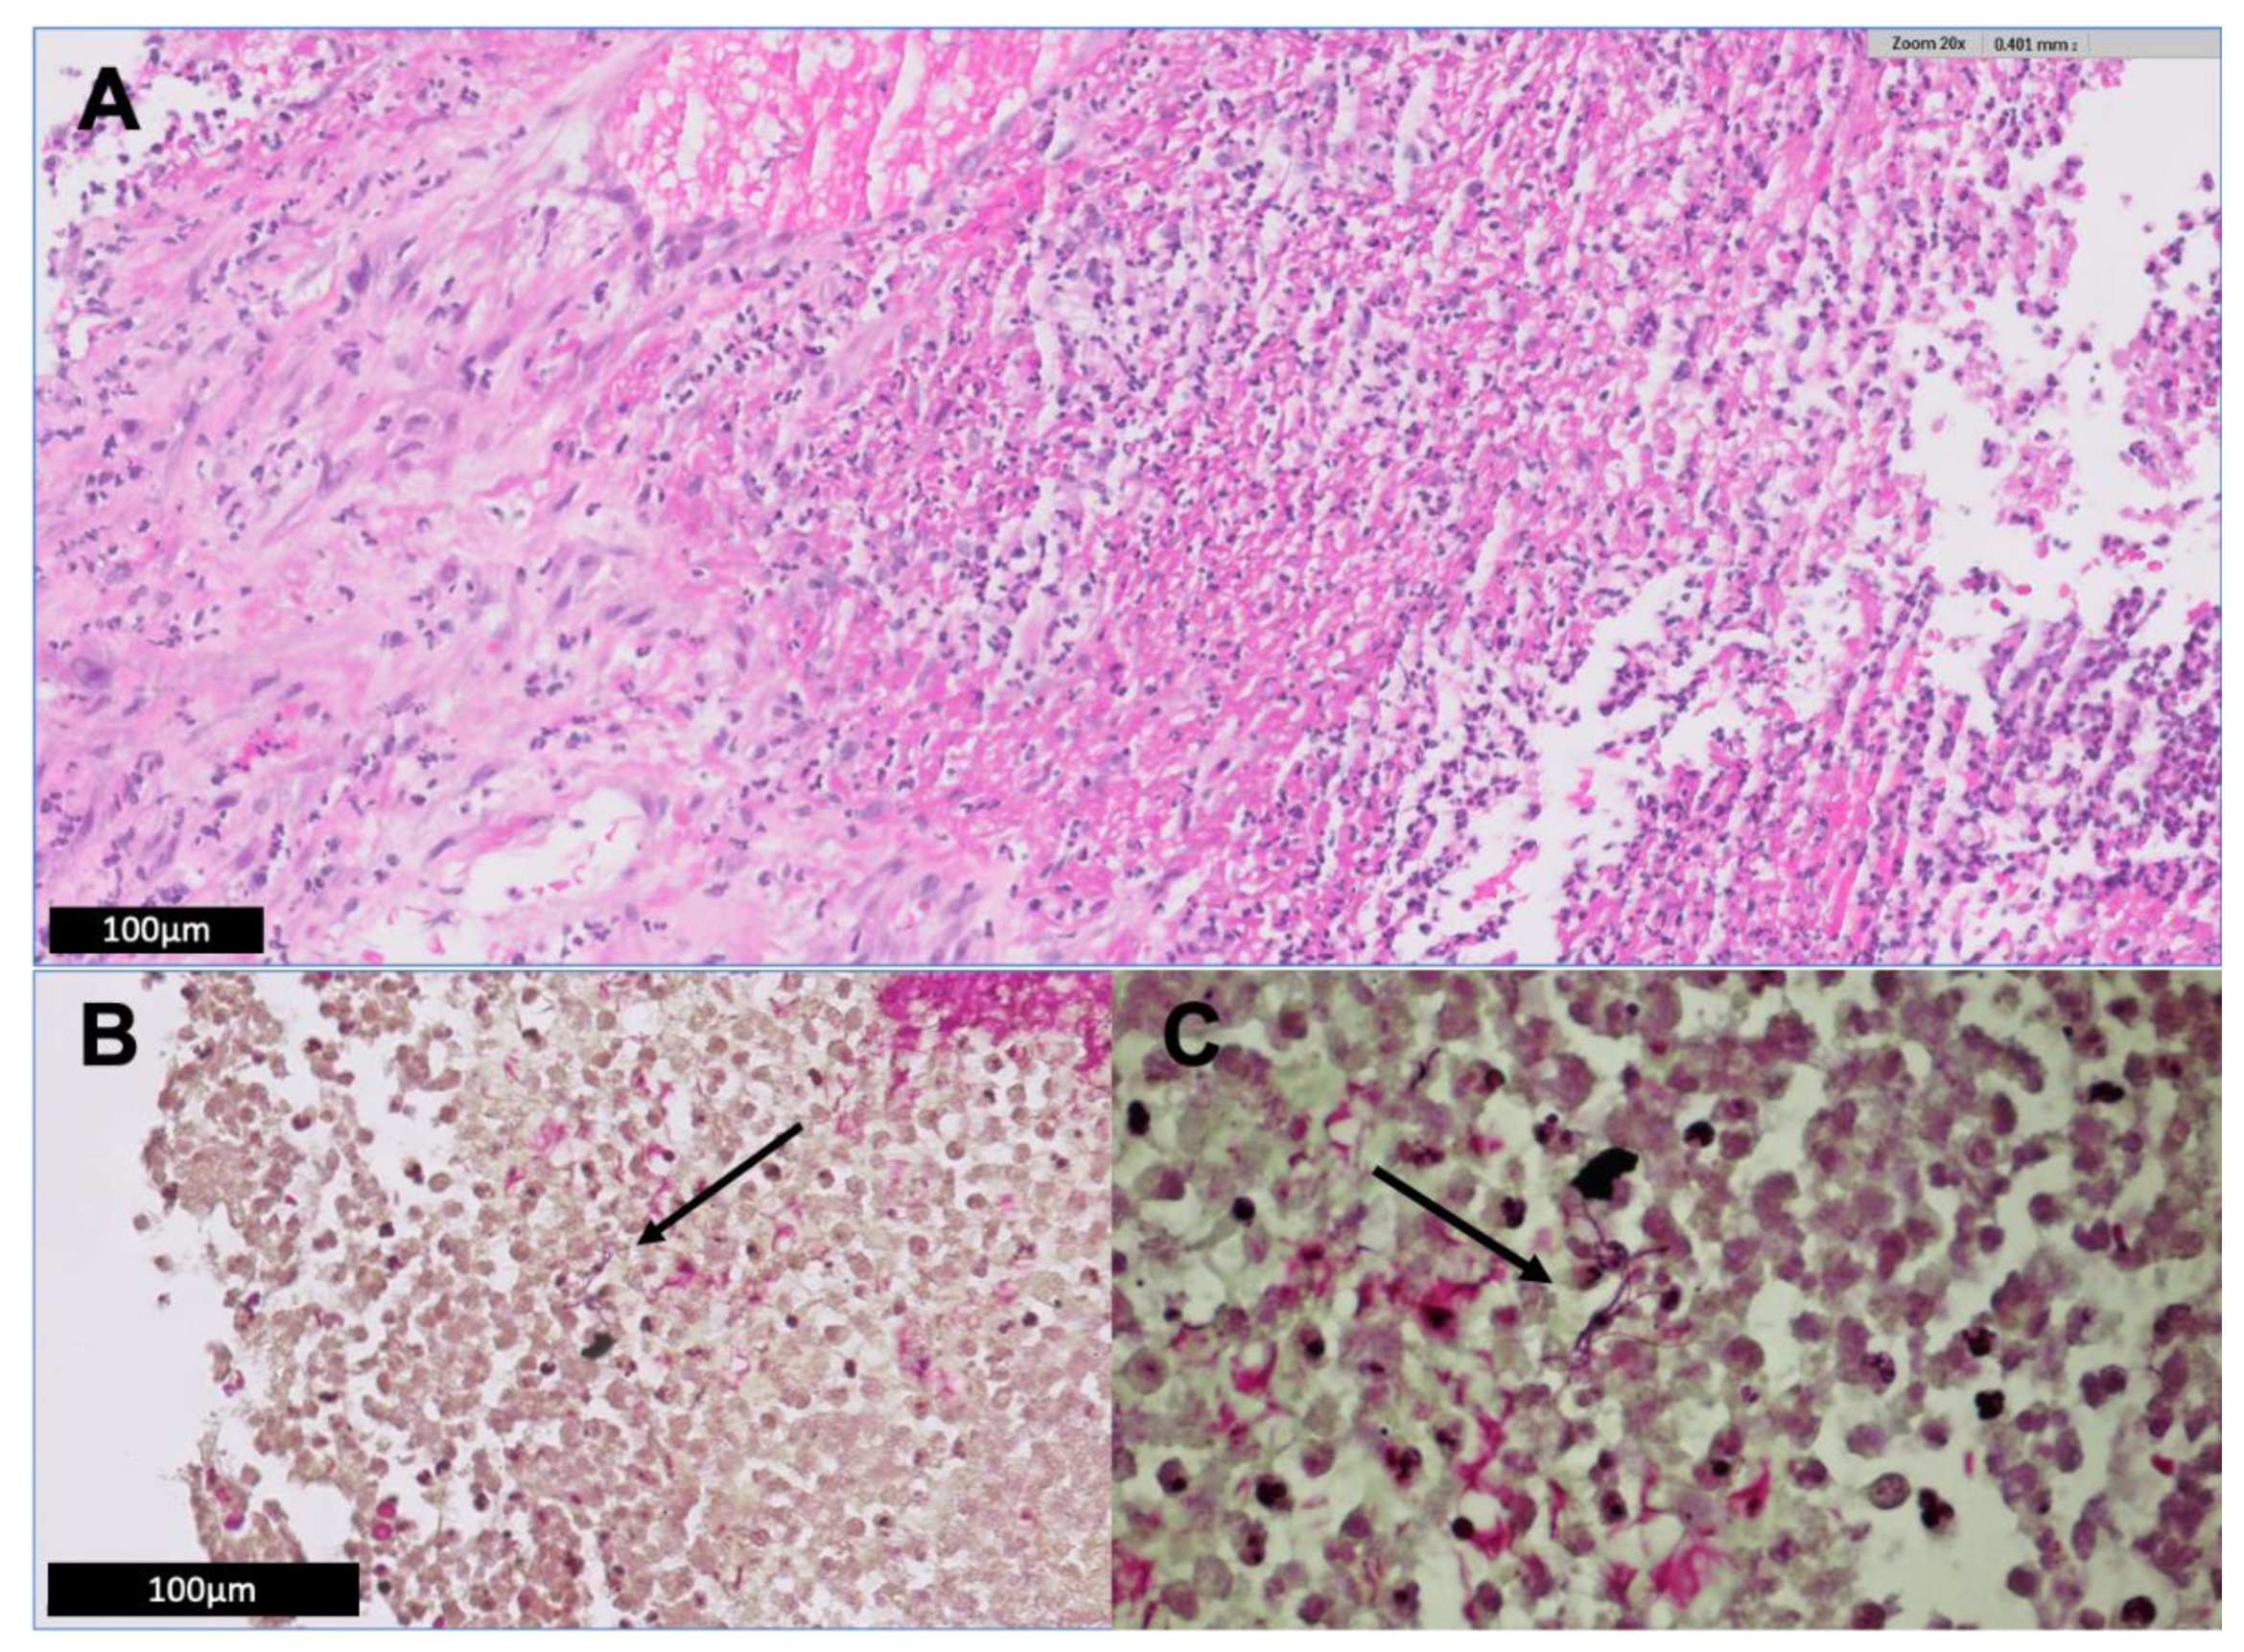

2. Illustrative Case Report